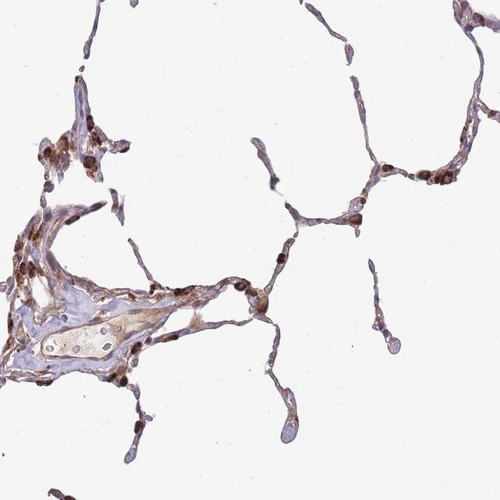

Immunohistochemical staining of human lung shows cytoplasmic positivity in pneumocytes .